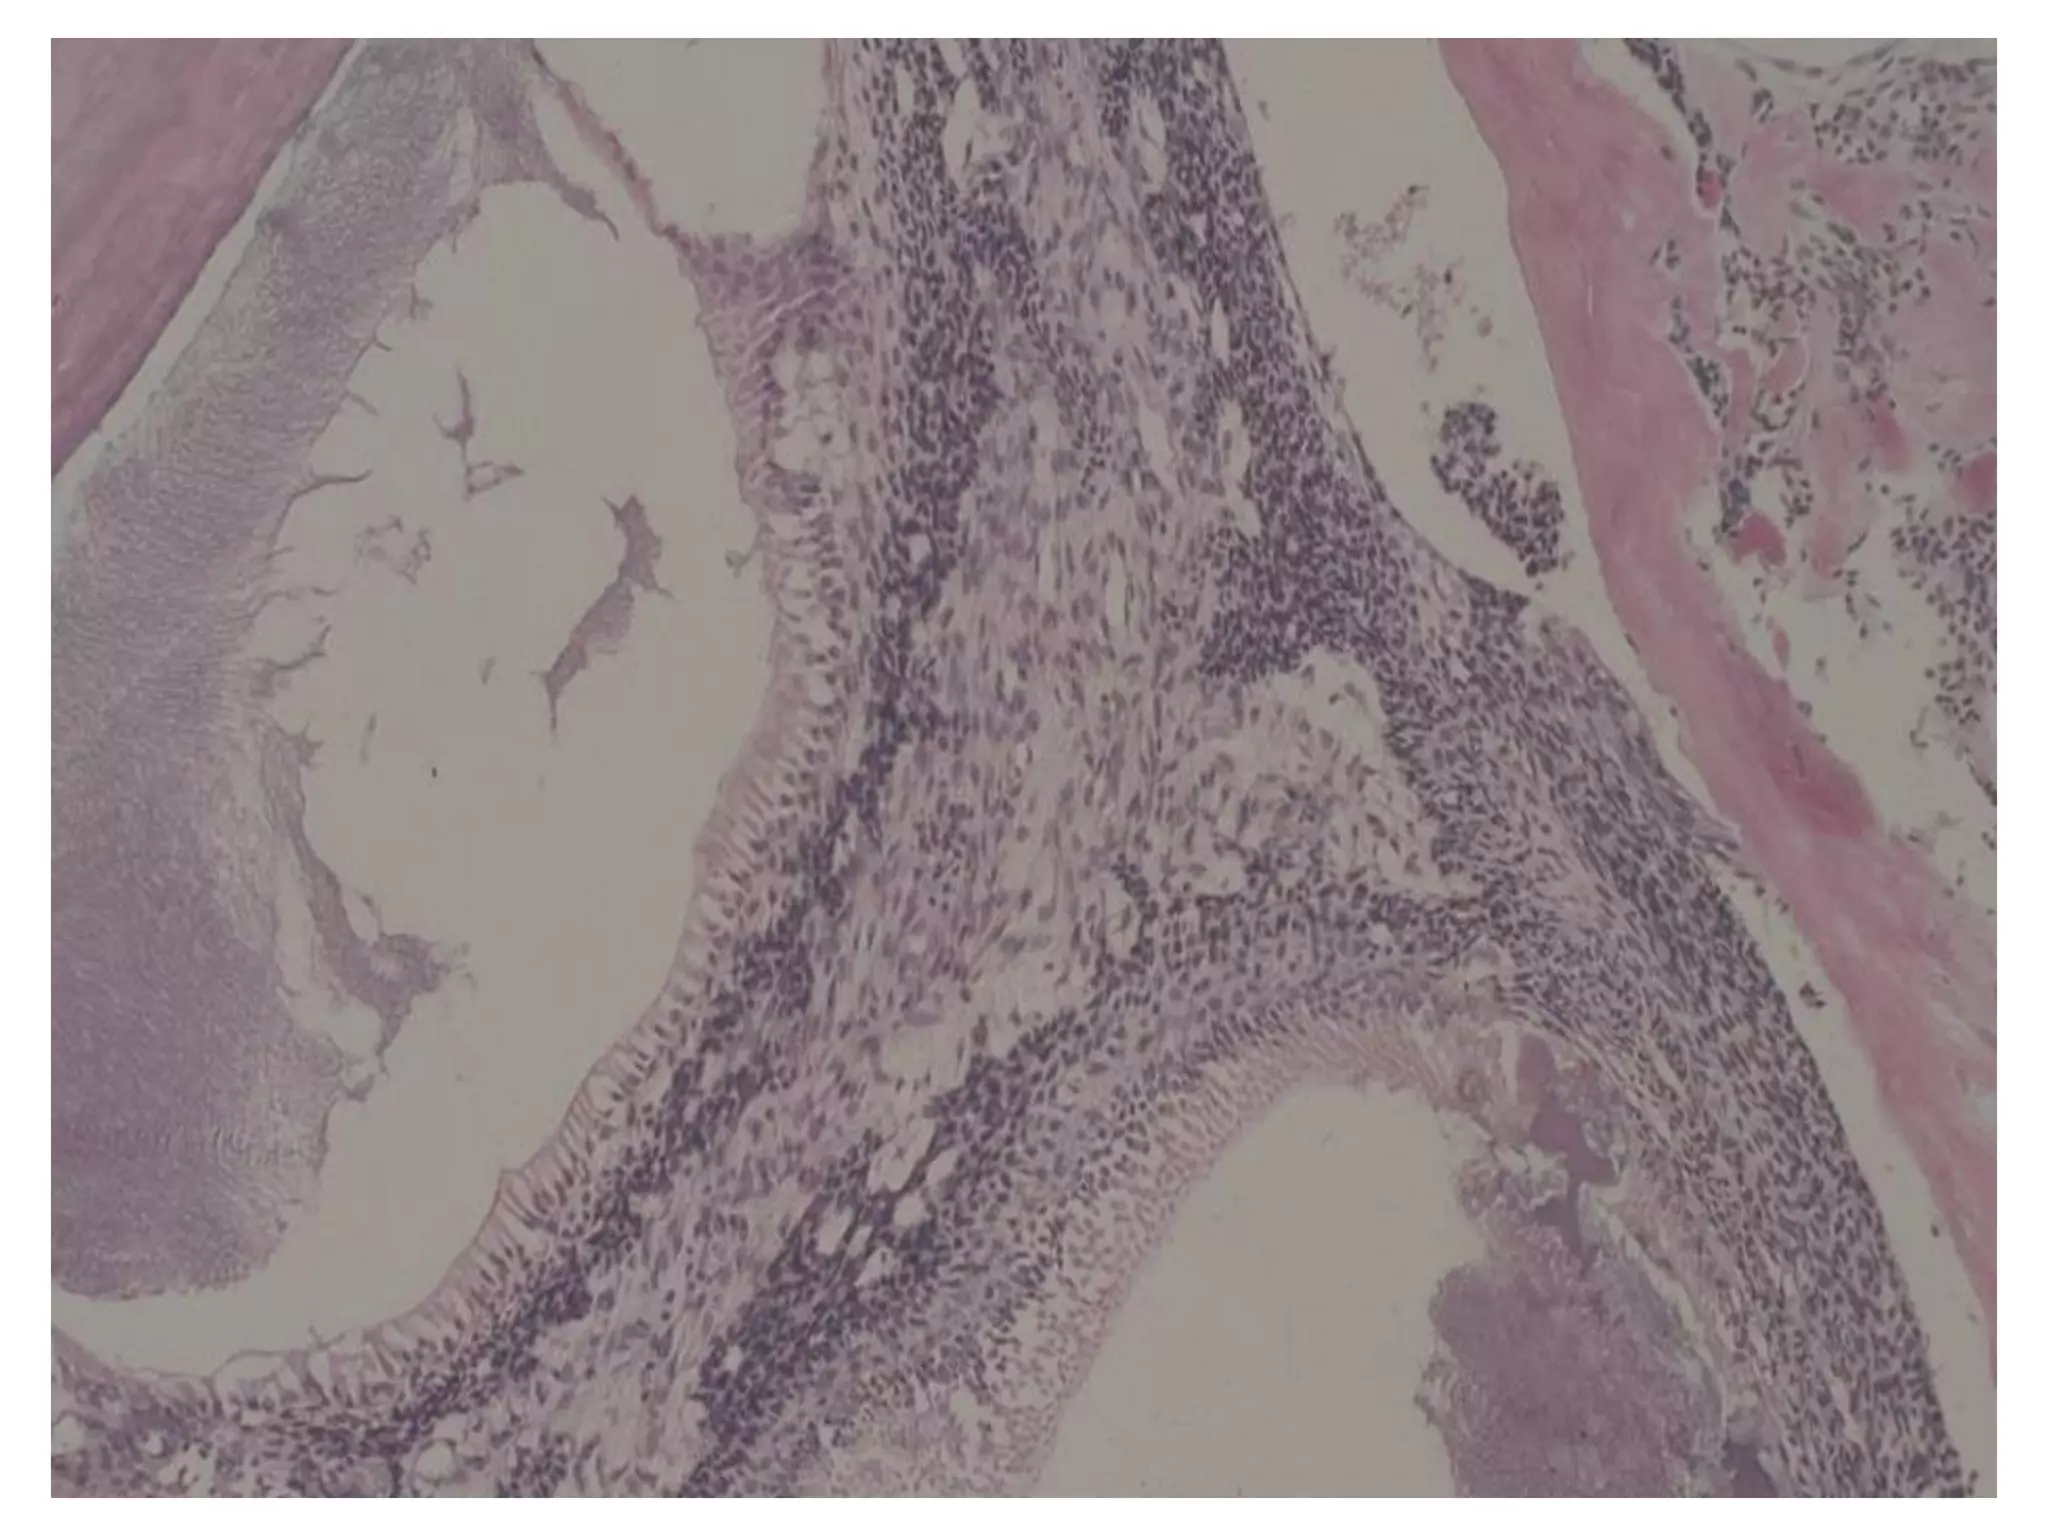

Giaûi phaãu beänh

 Coù nhieàu döôùi típ (subtypes) treân vi theå nhöng

chuùng thöôøng mang ít ñaëc tính cuûa khoái u.

 Thöôøng gaëp nhaát laø daïng nang (follicular type) vaø

daïng ñaùm roái (plexiform type).

 U men ñaëc daïng nang goàm caùc ñaûo teá baøo bieåu moâ

gioáng cô quan men naèm trong moâ lieân keát sôïi tröôûng

thaønh.

 U men ñaëc daïng ñaùm roái goàm caùc daây (cords) bieåu

moâ taïo raêng daøi thoâng nhau hoaëc caùc laù (sheets)

bieåu moâ lôùn hôn. Moâ ñeäm loûng leõo vaø nhieàu maïch

maùu hôn.

plexiform type

Moâ ñeäm nhaày